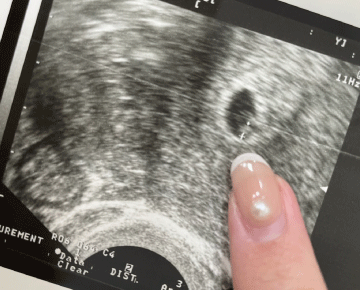

這是來自中國浙江的小燕子,懷孕成功的超音波照片,小燕子看到時的超級感動的!因為從結婚前就非常想要孩子的她,在結婚後和老公照表操課,卻還是沒有一絲懷孕的跡象…因為年紀已經到了高齡產婦的年齡,心急之下,她和老公決定直接求助專業醫師的幫助。在大陸時,經檢查之後,嘗試了試管嬰兒療程~